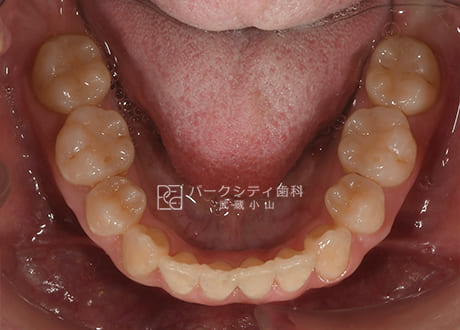

下顎術前

下顎術中